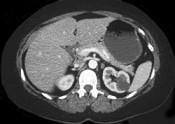

问题 女性,最近感腰部胀痛,体检发现B超右肾正常,左肾有一囊肿,双肾体积不增大,尿常规、肾功能正常,无家族病史,CT表现入图所示,最可能考虑为 ( )

选项 A.肾积水 B.多囊肾 C.多发性肾囊肿 D.肾肿瘤 E.肾结核

答案 C